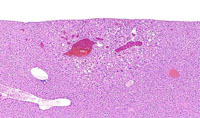

Angiectasis (peliosis hepatis, telangiectasis) is an incidental finding occasionally noted in aging mice. In extensive lesions, atrophy of adjacent hepatocytes may be seen. The lesions consists of dilated sinusoidal spaces lined by normal endothelial cells and filled with blood cells in immersion-fixed specimens. This lesion is occasionally associated with hepatocellular neoplasms. Angiectasis typically consists of smaller blood channels than is seen in hemangiomas. Also, angiectatic vascular channels are often not associated with endothelial cell proliferation as is seen in hemangiomas.

These examples represent medium magnification views of angiectasis.